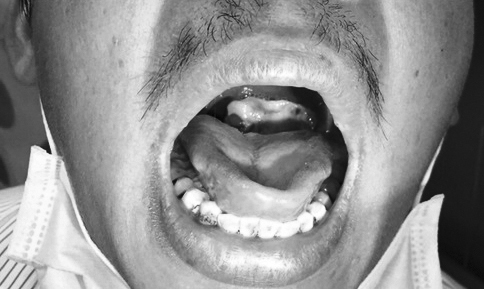

Ngày 12/11, Bệnh viện Bệnh Nhiệt đới TP.HCM cho biết, bệnh viện này vừa điều trị cho anh T.M.T. (30 tuổi, ở Long An) nhập viện trong tình trạng sốt, ho khan, họng có nhiều giả mạc. Sau khi thăm khám bác sĩ chẩn đoán chàng trai mắc bệnh bạch hầu. Và đây là ca đầu tiên trong năm mà bệnh viện ghi nhận được đến hiện tại.

Bác sĩ Nguyễn Thanh Phong, Trưởng khoa Nhiễm D, Bệnh viện Bệnh Nhiệt đới TP.HCM cho biết, sau 2 tuần điều trị, sức khỏe bệnh nhân cải thiện song cần theo dõi liên tục nguy cơ biến chứng lên tim.

Bệnh nhân bị bạch hầu đang được điều trị tại BV Nhiệt đới TP.HCM là ca đầu tiên ghi nhận từ đầu năm đến nay.

Bác sĩ Phong cho rằng, bệnh bạch hầu thường gặp ở trẻ nhỏ từ 1 - 10 tuổi nhưng cũng xuất hiện ở người lớn. Bệnh thường gây nhiễm trùng cấp tính, có thể đưa đến biến chứng tim và tử vong. Ngoài ra, bệnh cũng có thể dẫn đến thoái hóa thận, hoại tử ống thận, chảy máu lớp tủy và vỏ thượng thận.

Biến chứng viêm cơ tim có thể xuất hiện sớm ở những ngày đầu của bệnh, thậm chí sau 3 -5 tuần khi bệnh hồi phục.

Bệnh có thể lây lan qua đường hô hấp, nếu nước bọt người bệnh văng trúng người xung quanh cũng có thể truyền bệnh. Khoảng 2-5 vi khuẩn bạch hầu sẽ phát bệnh đối với người bị dính nước bọt từ người bệnh

Hiện, bệnh bạch hầu thuộc dạng bệnh xếp vào loại bệnh được tiêm chủng mở rộng quốc gia. Chính vì vậy, chuyên gia khuyến cáo phụ huynh nên tiêm phòng đầy đủ cho trẻ. Bệnh nhân khi bị viêm họng và các triệu chứng ho sốt kéo dài không hết nên đi khám sớm và điều trị kịp thời.